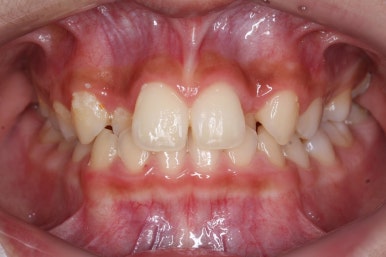

처음 내원 때의 입안 모습입니다.

영구치는 모두 맹출이 되어있었고 아랫니는 윗니에 비해 매우 가지런한 편이였습니다.

윗니 중에서도 앞니가 매우 삐뚤하고 특히 작은 앞니 양쪽 모두가 아래 앞니보다 안쪽에 들어가 있는 모습입니다.

이번 환자분은 송곳니가 거의 자기위치에 나오게 되면서 약한 작은 앞니를 밀어낸 경우입니다.

송곳니는 거의 제자리에 나오긴 했지만 작은 앞니가 안쪽으로 쏙 들어가 있기 대문에 상대적으로 덧니처럼 보이게 되는 것입니다.